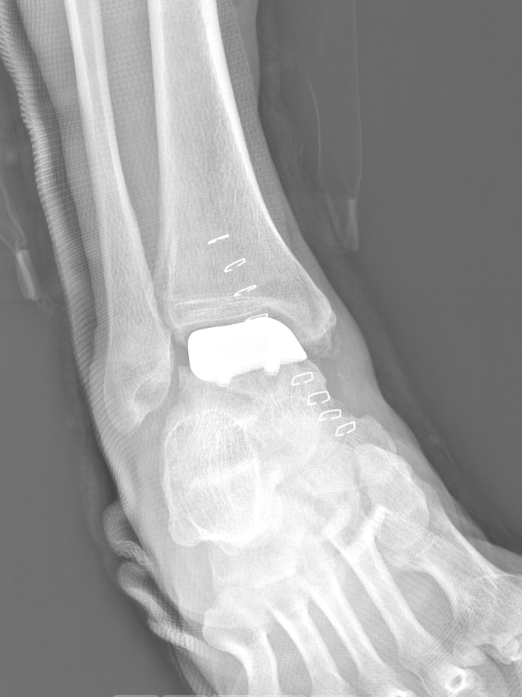

武勇主任团队给他做了3D打印导板辅助下人工全踝关节置换术。

这种手术适合踝关节病严重的患者,通过替换病变的关节结构,能帮着缓解疼痛、恢复关节活动,让老人日常走路更自在些。

术后侧位X线

术后正位X线